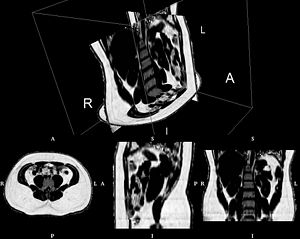

MRI-Only Based Radiotherapy Treatment Planning for the Rat Brain on a Small Animal Radiation Research Platform (SARRP)

Publication: PLoS One. 2015 Dec 3;10(12):e0143821. PMID: 26633302 | PDF Authors: Gutierrez S, Descamps B, Vanhove C. Institution: Medical Image and Signal Processing Group, Ghent University-iMinds Medical IT department, Ghent, Belgium. Background/Purpose: Computed tomography (CT) is the standard imaging modality in radiation therapy treatment planning (RTP). However, magnetic resonance (MR) imaging provides superior soft tissue contrast, increasing the precision of target volume selection. We present MR-only based RTP for a rat brain on a small animal radiation research platform (SARRP) using probabilistic voxel classification with multiple MR sequences. Six rat heads were imaged, each with one CT and five MR sequences. The MR sequences were: T1-weighted, T2-weighted, zero-echo time (ZTE), and two ultra-short echo time sequences with 20 μs (UTE1) and 2 ms (UTE2) echo times. CT data were manually segmented into air, soft tissue, and bone to obtain the RTP reference. Bias field corrected MR images were automatically segmented into the same tissue classes using a fuzzy c-means segmentation algorithm with multiple images as input. Similarities between segmented CT and automatic segmented MR (ASMR) images were evaluated using Dice coefficient. Three ASMR images with high similarity index were used for further RTP. Three beam arrangements were investigated. Dose distributions were compared by analysing dose volume histograms. The highest Dice coefficients were obtained for the ZTE-UTE2 combination and for the T1-UTE1-T2 combination when ZTE was unavailable. Both combinations, along with UTE1-UTE2, often used to generate ASMR images, were used for further RTP. Using 1 beam, MR based RTP underestimated the dose to be delivered to the target (range: 1.4%-7.6%). When more complex beam configurations were used, the calculated dose using the ZTE-UTE2 combination was the most accurate, with 0.7% deviation from CT, compared to 0.8% for T1-UTE1-T2 and 1.7% for UTE1-UTE2. The presented MR-only based workflow for RTP on a SARRP enables both accurate organ delineation and dose calculations using multiple MR sequences. This method can be useful in longitudinal studies where CT's cumulative radiation dose might contribute to the total dose. |

Illustration of a CB-CT and five MR images of the same animal. a) Coronal CB-CT image and (b)-(f) biased field corrected and masked coronal MR images using a T1-weighted (b), T2-weighted (c), ZTE (d), UTE1 (e) and UTE2 (f) sequence. All CB-CT images were first co-registered using 3D Slicer version 3.6.3 by rigid body transformations using normalized mutual information. |